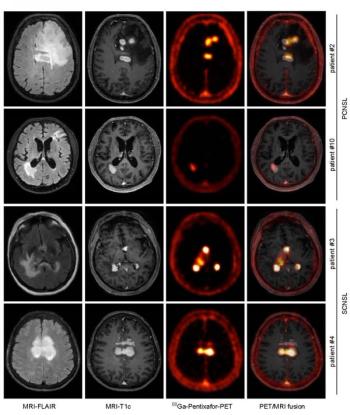

68Ga-pentixafor can clearly distinguish between healthy and malignant tissue on both CT and MRI scans.